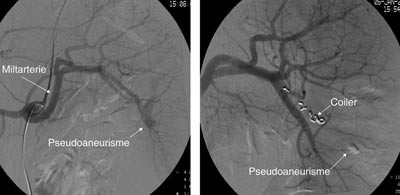

Pasient 1. En 16 år gammel gutt ble henvist til lokalsykehuset med spørsmål om miltskade. Han hadde seks dager tidligere falt under fotballtrening. Pasienten kom gående og klagde over magesmerter. CT-undersøkelse supplert med arteriell kontrastfase gav tydelig fremstilling av en rund, velavgrenset og høyattenuerende lesjon (fig 2a). På bildene fra vanlig venøs kontrastfase var denne strukturen dårligere fremstilt (fig 2b). Pseudoaneurisme ble mistenkt. Skaden ble vurdert som grad IV. Pasienten ble overflyttet til Ullevål universitetssykehus hvor det ble utført angiografi som bekreftet diagnosen. Deretter foretok man embolisering (fig 3). Prosedyren var vellykket og pasienten ble utskrevet etter én uke.

I litteraturen er det beskrevet redusert sensitivitet og spesifisitet for pseudoaneurismer ved CT-undersøkelse sammenholdt med angiografi (8), men undersøkelsene er som oftest kun gjort i venøs kontrastfase. I flere studier er det benyttet forsinkelse fra kontrastinjeksjon til bildeopptak på mellom 70 og 85 sekunder som tilsvarer sen eller venøs kontrastfase (1, 9, 10). CT-bildene fra undersøkelsen av pasient 1 illustrerer at dette kan vanskeliggjøre diagnostikken. I tillegg er det viktig å vite at vaskulære lesjoner kan presentere seg forsinket. Det viser bildene av pasient 2. CT-undersøkelse i arteriell og venøs fase etter 5 – 7 dager i tillegg til undersøkelse ved innkomst er derfor anbefalt (2, 6).